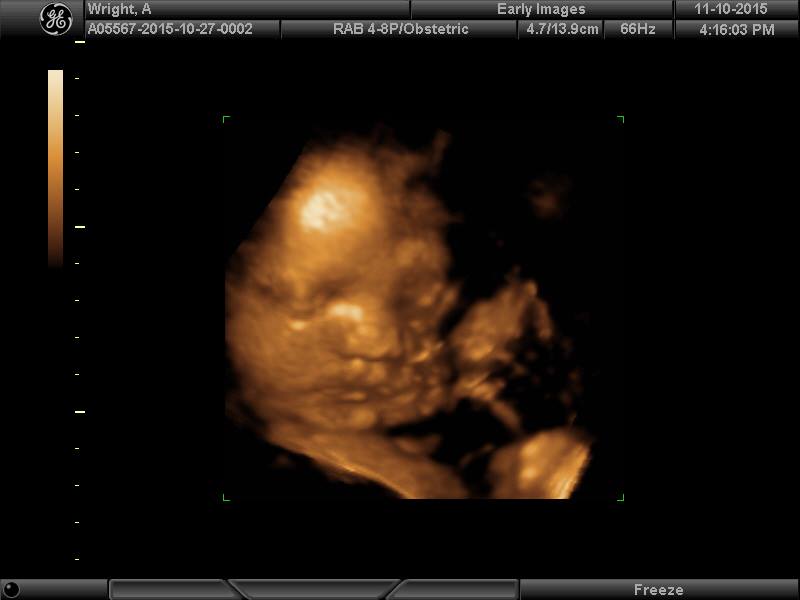

3rd Tri Ultrasound Sharing

Re: 3rd Tri Ultrasound Sharing